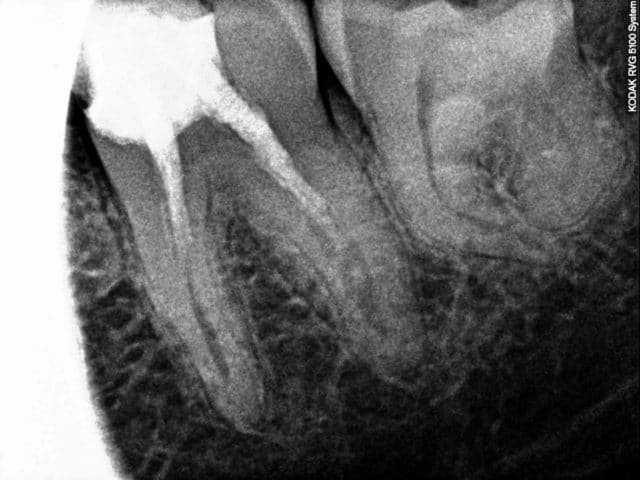

Patient vus à un mois d'intervalle pour des douleurs. Pas de devis miroboland, des CCM à 500 euros qui feront plaisir à santéclair ou à notre ministre de la mauvaise santé, secteur campagne.

Vus la premiere fois pour un debut d'infection sous 47 un samedi à la fermeture, demontage du screw post, allésage laissée ouverte avec une prescription puis retours chez mon confrére.

Puis un mois plus tard retour un samedi pour des douleurs suite à l'obturation de 46, endo metasonne, cône de 2%, canal ML et DL non preparés, démontage du cône DV avec le coton laissé dans la chambre.

Il n'ai pas besoin de faire des devis delirant ou de partiquer des tarifs de prothése excessifs pour mal faire notre travail.

Il a l'air doué ce dentiste ... il aurait pu faire la couronne sans faire l'endo sur la 6 et on fait semblant de pas avoir vu la fracture d'instrument sur la 7

Les patients sont mieux armés pour discuter de la réalité d'un devis gonflé, que sur la qualité des soins de bases. La 8 ne fait pas mal et si le ML ne saignait pas encore dans la dent "obturée", le traitement serait allé à son terme avec des CCM à 500 euro réalisées sur çà.